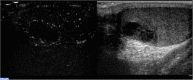

Background: Contrast-enhanced ultrasound (CEUS) is a sonographic technique that increases the diagnostic accuracy of ultrasound and color Doppler ultrasound (CDUS) when studying testicular abnormalities. However, its role in clinical practice is still debatable because there are no accepted standards regarding how and when this technique should be used for patients with testicular disease.

Results: Strong enhancement of neoplastic lesions (both benign and malignant) during CEUS aids in differential diagnosis with non-neoplastic lesions, which usually appears either nonenhanced or enhanced in a manner similar to that of the surrounding parenchyma. CEUS enhancement has a high predictive value in the identification of neoplastic lesions, whereas a similar or complete absence of enhancement may be interpreted as strong evidence of benignity, although there are exceptions. Literature on quantitative analysis is still scarce, though promising, particularly in distinguishing benign from malignant neoplasms. Furthermore, CEUS may be useful in many emergency situations, such as acute scrotum, blunt scrotal trauma, and focal infarction of the testis. Finally, CEUS can help increase the probability of sperm recovery in azoospermic males.